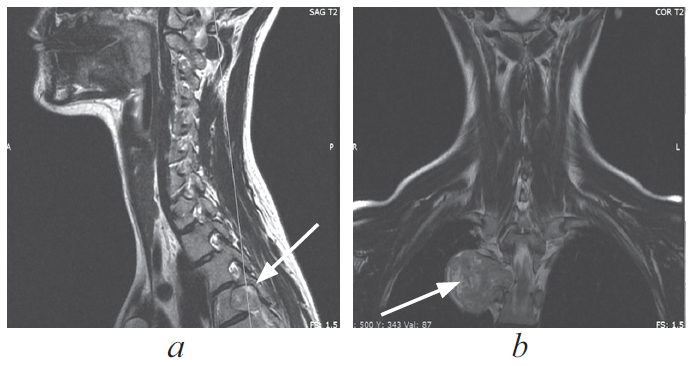

Паравертебральные опухоли медиастинальной локализации — обширная группа патологических процессов с различной гистологической картиной и биологическим поведением, хирургическим лечением при которой занимаются врачи разных специальностей, таких как нейрохирурги и хирурги-онкологи. В настоящее время наиболее предпочтительным методом хирургического лечения данных объемных образований принято считать торакоскопическое удаление, ввиду наименьшей травматичности, меньшего количества осложнений и сокращения времени послеоперационного восстановления пациентов. Представлен клинический случай хирургического лечения пациентки с гигантской паравертебральной опухолью, исходящей из IV грудного корешка. Опухоль стала случайной находкой при выполнении плановой флюорографии. Очаговой неврологической симптоматики не отмечалось. Учитывая топографо-анатомические особенности объемного образования, пациентке было проведено комбинированное двуэтапное оперативное вмешательство: сначала выполняли ламинэктомию и удаление фораминального компонента опухоли из заднего доступа, затем одно портовое видеоассистированное торакоскопическое удаление медиастинально расположенного фрагмента опухоли. Операция проходила в условиях коллабированного легкого на стороне вмешательства. В послеоперационном периоде неврологического дефицита не отмечено, по данным контрольной интроскопии опухоль удалена тотально. По результатам гистологического исследования — нейрофиброма (Grade I). Приведенный клинический пример показывает успешную коллаборацию спинальных и торакальных хирургов, а также иллюстрирует возможности современной минимально инвазивной хирургии.